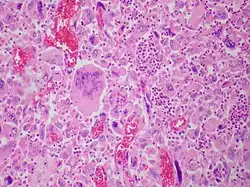

| Pulmonary giant cell carcinoma represents a rare variety of non-small cell lung carcinoma that is characterized by the presence of numerous tumor giant cells and an influx of inflammatory cells that are mostly polymorphonuclear leukocytes admixed with macrophages. The dense oval aggregates of polymorphonuclear leukocytes seen in this image are probably located in the cytoplasm of tumor giant cells (emperiopolesis) that have been sectioned in a plane that does not include their nuclei. | |

The characteristic feature of this highly lethal malignancy is the distinctive light microscopic appearance of its extremely large cells, which are bizarre and highly pleomorphic, and which often contain more than one huge, misshapen, pleomorphic nucleus ("syncytia"), which result from cell fusion.

Both "tumor cell-tumor cell" and "leukocyte-tumor cell" emperipolesis (i.e. active penetration of the latter by the former) is very commonly seen in cases of GCCL.[12]